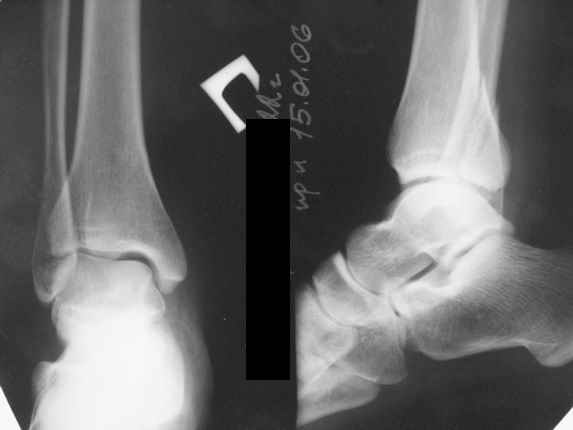

Тему неоднократно разбирали (см. архив), как всегда, недостаточны ренгенологические исследования - кроме прямого и боковых снимков, еще нужна косая ренгенограмма для определения ankle mortise, без мортиз снимка трудно определить высоту и ротацию малоберцовой. (снимки)

Ренгенология даст ответ как классифицировать перелом, на сегодня применяется классификация “Lauge Hansen fracture classification SER supination-external rotation или supination-eversion classification Danis

Weber А, В, С.”

Показания для фиксации: укорочения и ротация малоберцовой, особенно обращают внимание на любой подвывих таранной кости: неустраненый подвывих впоследствии приводит к раннему артрозу. Задний край фиксирует тогда, когда перелом составляет около 25% суставной поверхности голеностопного сочленения и смещение более 2мм.

По снимку ваш случай относится к Weber В, фиксацию производят восстановлением длины малоберцовой кости, под ренгеном (ЭП)контролем, для этого я предпочел бы латеральный доступ, остеотомия по линии перелома, удлинение малоберцовой засчет скоса линии остеотомии, компрессия “lag technique”по линии остеотомии и фиксацию провести латеральной пластиной. Отдельный задний доступ, остеотомия по линии перелома, репозиция и фиксация заднего края вашим предпочтительным методом: 3.5мм шурупом с шайбой или пластиной Antiglide Butress